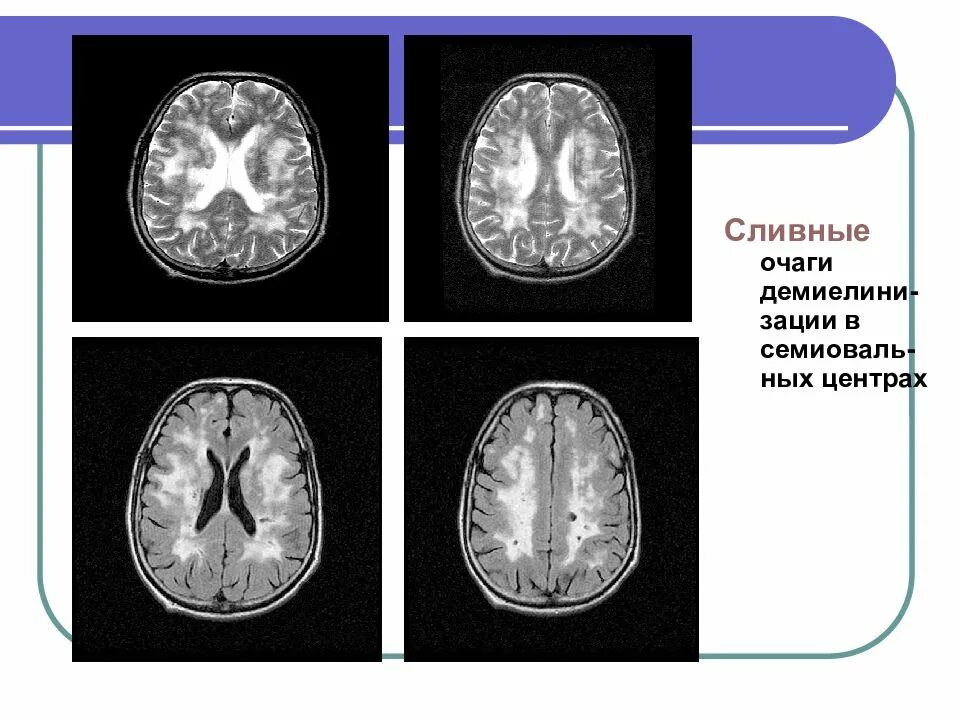

Демиелинизирующее заболевание головного мозга что это такое